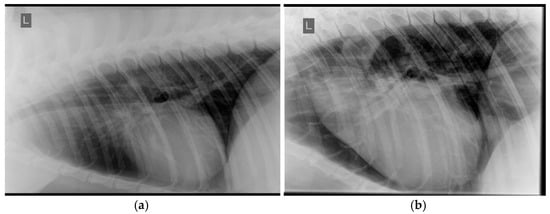

3.2. Systemic Hypertension Lesions

- Nelson, O.L.; Reidesel, E.; Ware, W.A.; Christensen, W.F. Echocardiographic and radiographic changes associated with systemic hypertension in cats. J. Vet. Intern. Med. 2002, 16, 418–425. [Google Scholar] [CrossRef]